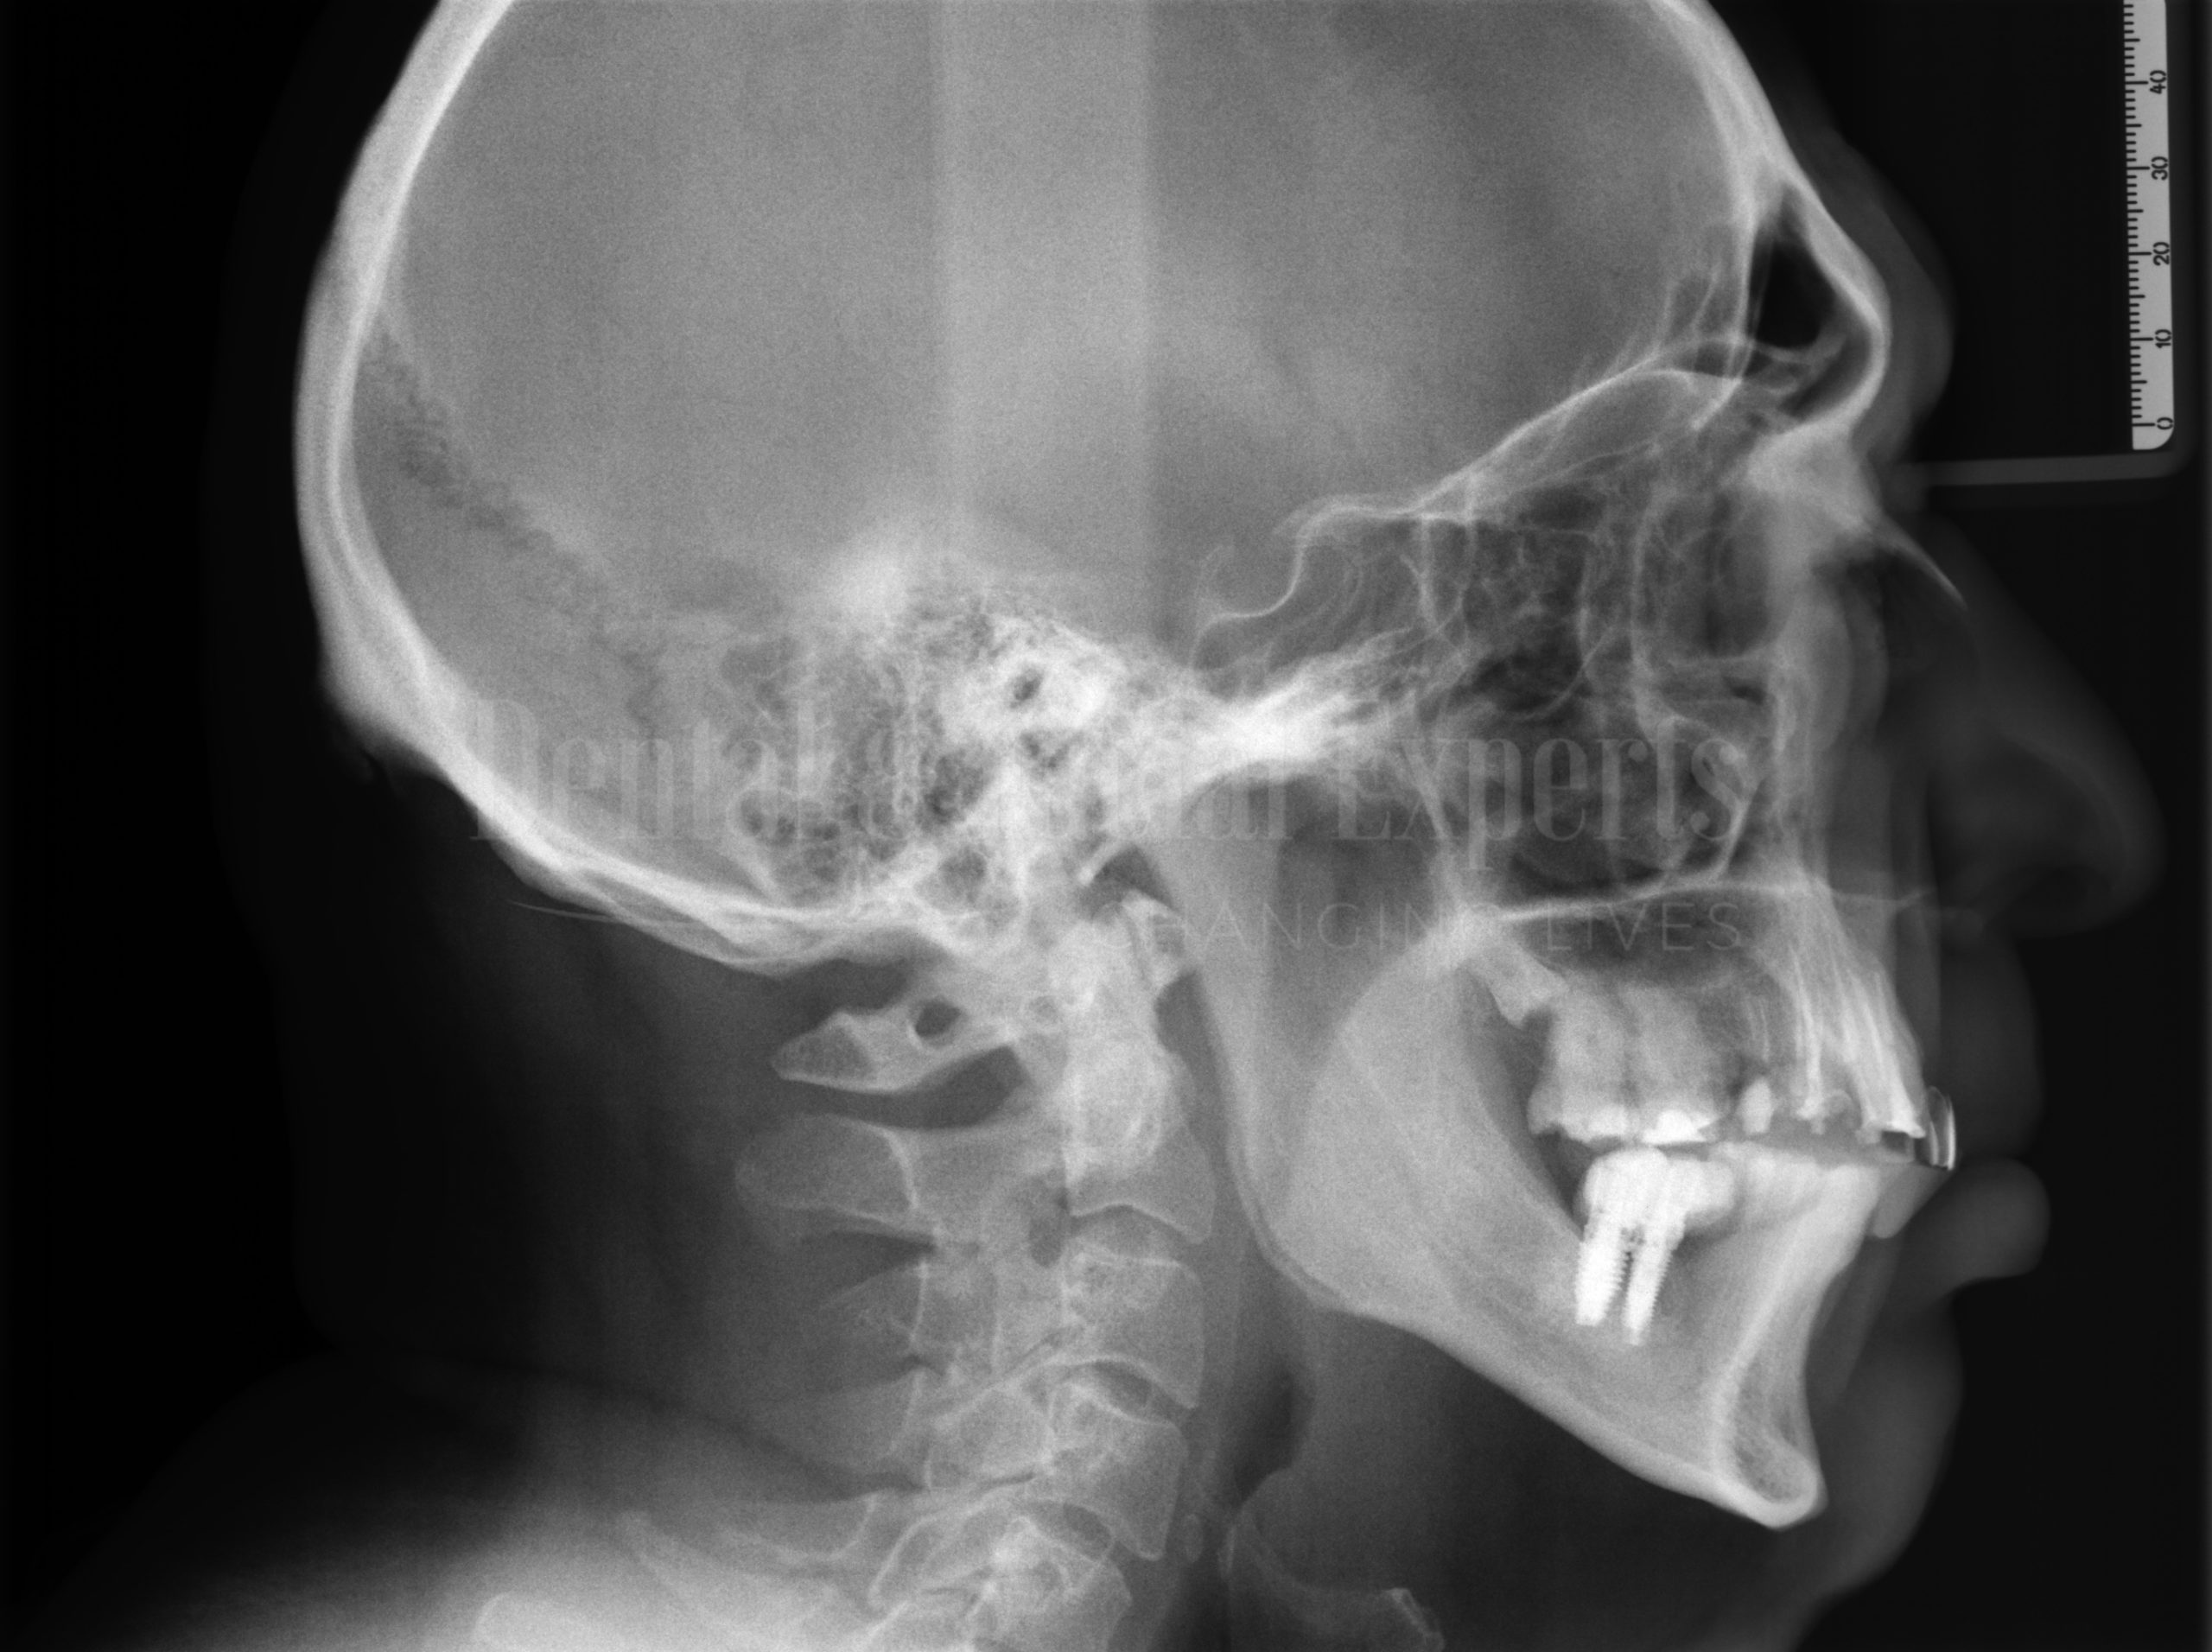

José-Cándido-P

José-Cándido-O

José-Cándido-F

TRATAMENTO

• APNEIA OBSTRUTIVA DO SONO

• CIRURGIA ORTOGNATICA BI-MAXILAR

• MENTOPLASTIA